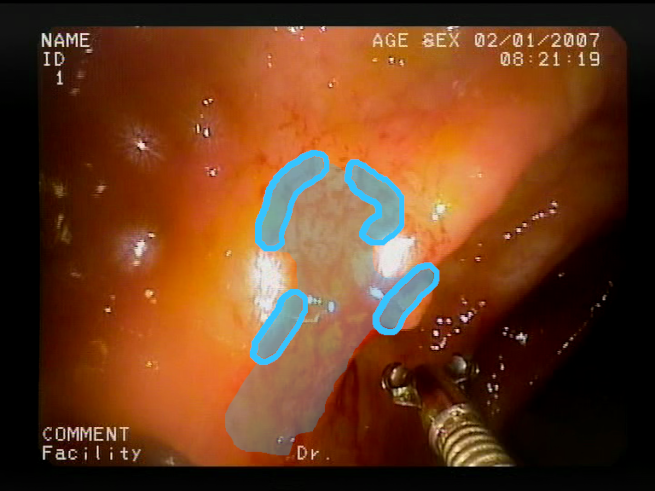

As a result of the design process, nine high-level features (denoted F1–F9) were defined. The features are proposed with simple definitions that also include exemplary images, presented in Table 1. For each image, a blue annotation is presented, illustrating the image regions where the feature is hypothetically present.

Table 1.

Definitions of the nine proposed visual features of endoscopic bleeding. For each image, a blue annotation is presented, which illustrates the area of the image where the feature is hypothetically present.